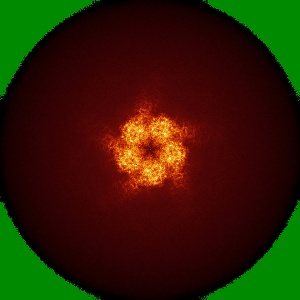

CryoEM structure of a human gamma-aminobutyric acid receptor, the GABA(A)R-beta3 homopentamer, in complex with histamine and megabody Mb25 in lipid nanodisc

Single-particle1.7 Å

Sample: Human GABA(A)R-beta3 homopentamer in complex with Megabody-25 in lipid nanodisc

Single-particle cryo-EM at atomic resolution.